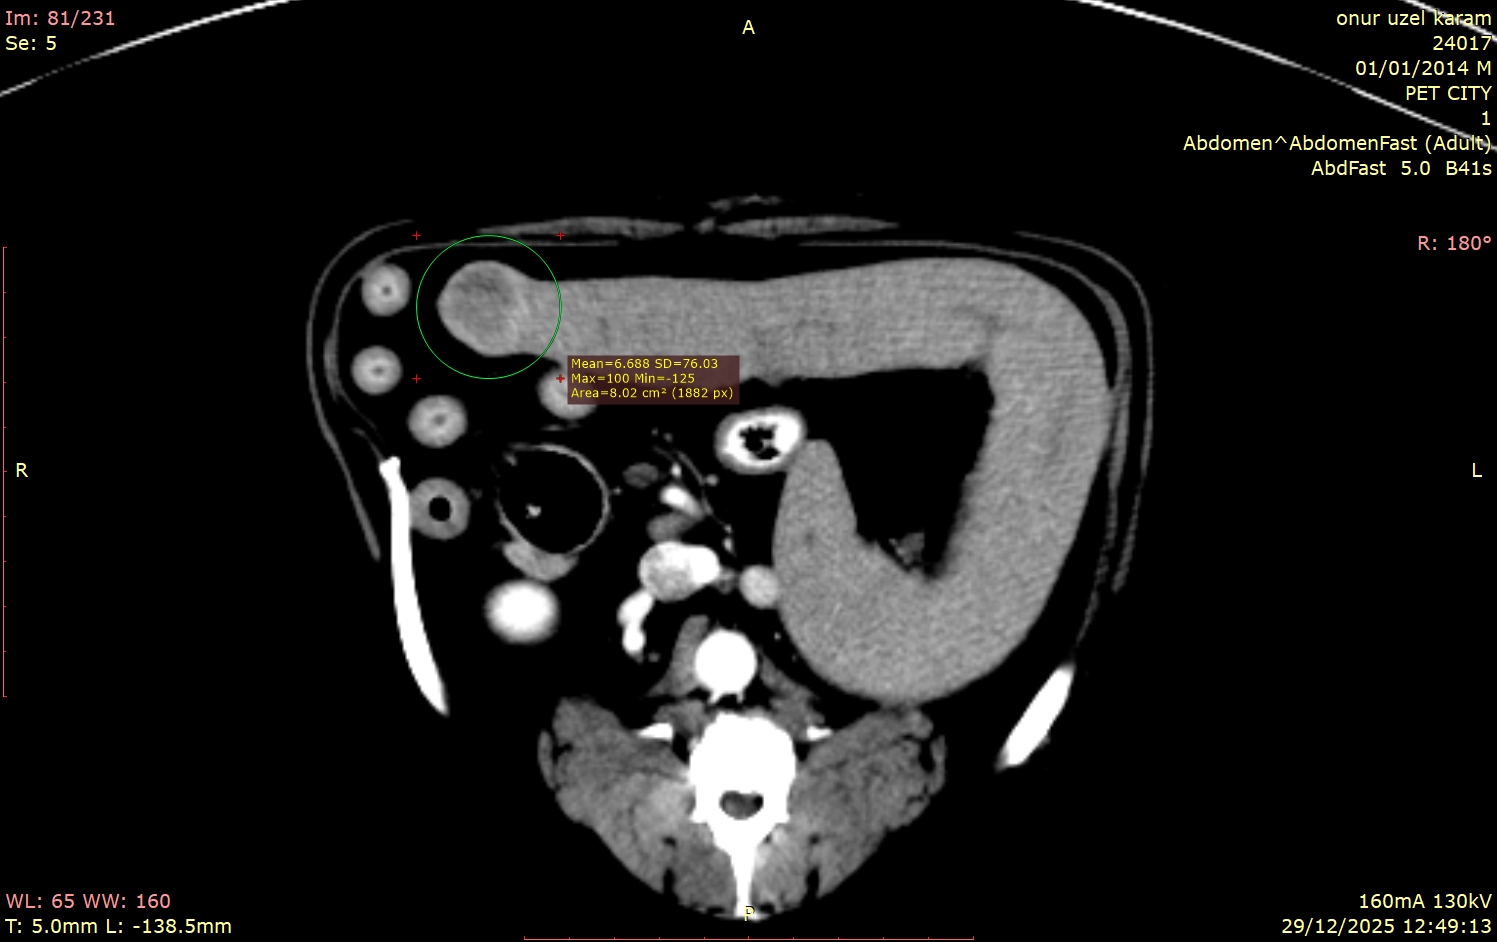

Kliniğimize prostat büyümesi şüphesiyle gelen sevimli dostumuzun hikayesi, doğru tanı araçlarının ne kadar hayati olduğunu bir kez daha kanıtladı. Rutin muayeneler ve klinik belirtiler bize bir yön gösterse de, vücudun içinde tam olarak neler olup bittiğini anlamak için bazen daha derinlemesine bir bakış gerekir. Bu vakamızda, teşhis için Bilgisayarlı Tomografi (BT) çekimine karar verdik. Ancak sonuçlar bize sadece prostatı değil, çok daha fazlasını anlattı.

Geleneksel görüntüleme yöntemlerinin aksine, tomografi bize vücudu katman katman, üç boyutlu bir hassasiyetle inceleme şansı verir. Bu teknoloji sayesinde, hekimlerimiz yalnızca şikâyet konusu olan bölgeyi (bu vakada prostatı) değil, o bölgeyle komşu olan tüm organları, doku yapılarını ve potansiyel riskleri tek bir taramada, en ince ayrıntısına kadar değerlendirebilir.

Hastamızın tomografi görüntülerini incelediğimizde, bizi şaşırtan ve tedavi planımızı kökten etkileyen detaylarla karşılaştık:

Bu vakadaki en kritik nokta, dalaktaki kitlenin tamamen "sessiz" olmasıydı. Hasta sahibinin fark edebileceği hiçbir semptom yoktu. Eğer sadece prostata odaklanıp ileri görüntüleme tekniklerini kullanmasaydık, dalaktaki bu lezyon gözden kaçabilirdi.

Tomografi çekilmemiş olsaydı, bu kitle belki de çok daha ileri bir evrede, tedavi şansının azaldığı bir dönemde karşımıza çıkacaktı. Bu vaka, tomografinin yalnızca mevcut problemi çözmekle kalmayıp, henüz belirti vermeyen gizli tehlikeleri de erken dönemde yakalama gücünü net bir şekilde göstermektedir.